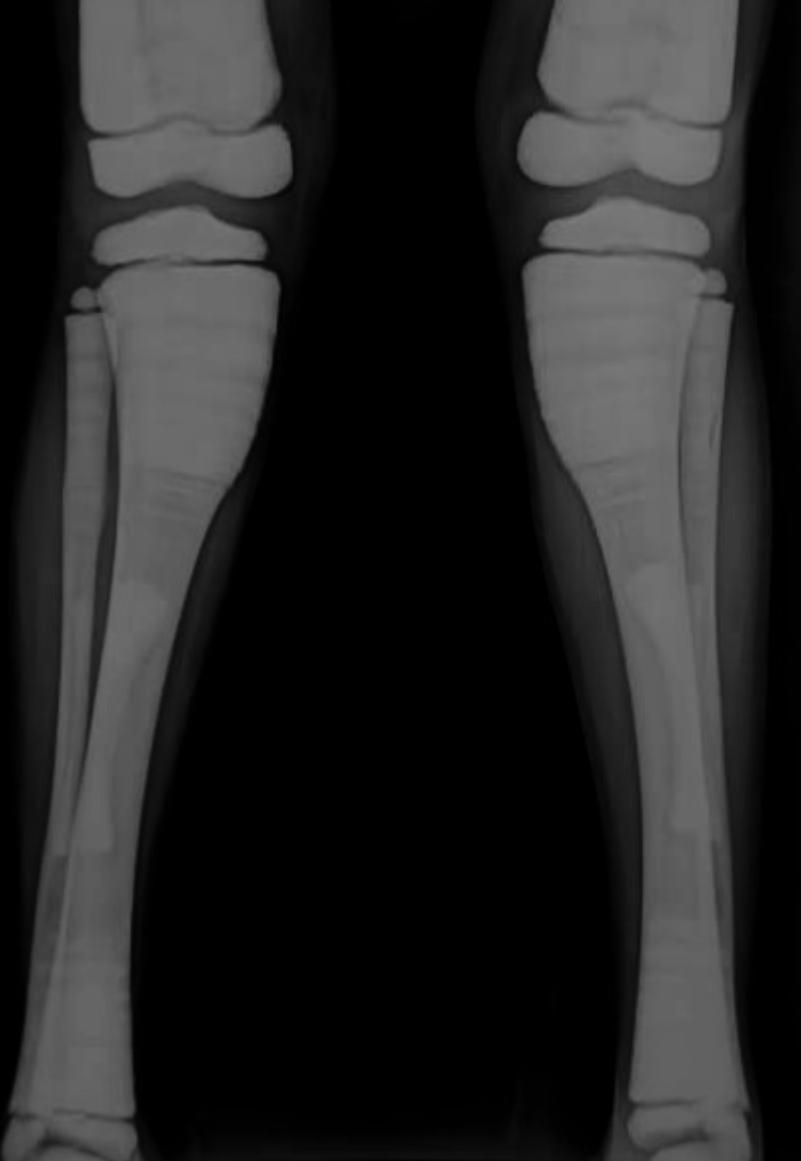

Obrazowanie stanowi podstawowy element diagnostyki osteopetrozy. Badanie RTG jest wystarczające do wstępnego rozpoznania, umożliwiając identyfikację typowych zmian, takich jak:

- uogólniona osteoskleroza (marble bone);

- obraz „kości w kości” (bone-in-bone);

- deformacja kolby Erlenmeyera w przynasadach kości długich.

Tomografia komputerowa umożliwia ocenę stopnia sklerotyzacji, deformacji czaszki i kanałów nerwowych oraz wykrywanie złamań patologicznych. Rezonans magnetyczny pozwala ocenić stopień zajęcia szpiku i ewentualne neuropatie nerwów czaszkowych, w tym ucisk nerwów wzrokowych i słuchowych.